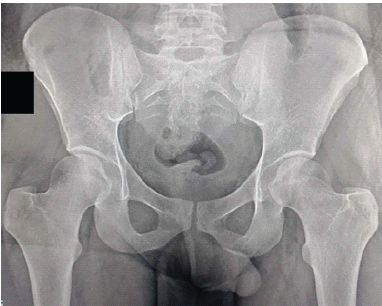

In view of his painful hip movements and the resulting functional limitation, surgery was advised. Following spinal anesthesia, in the lateral position, a linear incision was made along the iliac crest directly over the visible mass. The soft-tissue covering the tumor was dissected until the cartilaginous cap was exposed. The surrounding musculature was retracted, and the pedicle of the tumor was exposed. En bloc resection of the tumor mass through the base of the pedicle along with a periosteal margin of 0.5 cm was performed using curved osteotomes. Hemostasis was achieved by covering the bleeding bone with bone wax. Adequacy of resection was confirmed under fluoroscopy. The wound was closed in layers. Histopathologic examination confirmed the preoperative diagnosis of osteochondroma and showed the presence of hyaline cartilage with a fibrous perichondrial covering over osseous tissue (Fig. 5). The post-operative period was uneventful. There was no tumor recurrence at 1 year postoperatively (Fig. 6).

Figure 6: Post-operative anteroposterior pelvic radiograph of the second patient (Potential patient identifiers have been blacked out).